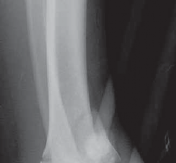

### FIG 3 • Low-energy spiral 43-A type fracture.

24. In contrast to high-energy patterns, rotational injuries ( FIG 3) cause spiral fractures of the distal tibia and fibula originating at the articular level. Intra-articular injury, if present, is typically simple and without comminution or impaction. NATURAL HISTORY